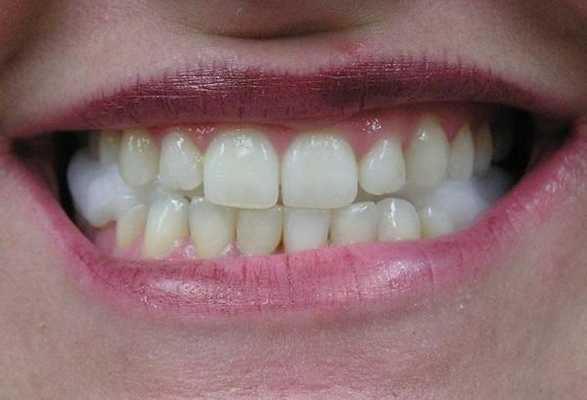

53-летняя женщина с ревматоидным артритом руки, запястья и плеча, обратилась за помощью по причине болевых ощущений в обоих ВНЧС. Она страдала от ревматоидного артрита в течение 1 года и принимала противовоспалительные препараты. КТ-диагностика подтвердила ревматоидное поражение обоих ВНЧС (фото 3а). У пациентки отмечалось ограниченное открывание полости рта (максимально до 23 мм), а болевые ощущения усиливались при движениях нижней челюсти. Для облегчения болевых симптомов было начато изготовление шины и проведен артроцентез обоих ВНЧС. Симптомы улучшились, однако у пациентки медленно начал развиваться передний прикус. Вертикальное перекрытие изменилось от начальных -6 мм до 0 мм (фото 3b).

b) Передний открытый прикус, который раздвинулся во время лечения с использованием шины.

с) Закрытие переднего открытого прикуса без прогрессирования нарушения в будущем.

Чтобы предотвратить прогрессирование патологии, была запланирована реконструкция ВНЧС. Во время операции было выполнено заднее перемещение верхней челюсти посредством остеотомии по Le Fort I, поскольку верхние передние зубы пациентки находились в состоянии протрузии. После резекции обоих мыщелков реконструкция ВНЧС с использованием протеза проводилась посредством вращения нижней челюсти против часовой стрелки для закрытия переднего открытого укуса (фото 3с). С момента операции на данный момент прошло уже 2 года, и в данный период не было отмечено никаких признаков воспалительного поражения области вмешательства. Симптомов прогрессирования открытого прикуса также не наблюдалось.